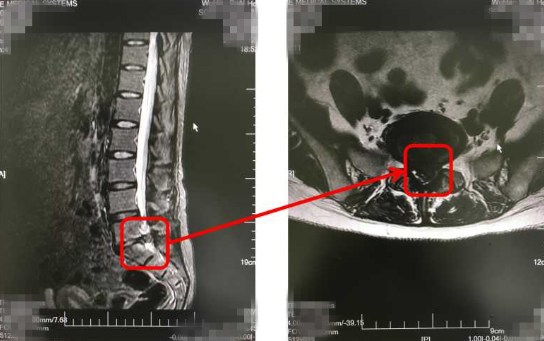

然而,休息了几天,却发现两条腿又痛又麻,而且这几天还连续便秘、肚子涨的难受。无奈之下,只好去医院进行检查,结果通过腹部B超等检查,并没有发现肠胃有什么问题,却在照腹部DR检查的时候发现,黄女士的腰椎间盘突出压迫到马尾神经,因而才会导致她下肢麻木疼痛、排便困难等症状,后经手术治疗,黄女士康复出院。

其实,如果腰椎间盘突出压迫到位于腰椎第二节以下的神经根,就会引发马尾神经损害,出现神经性功能障碍,从而导致便秘或大小便功能障碍等症状。

随着医疗技术的不断进步,目前脊椎内镜的微创手术,是手术治疗技术之一,通过一个直径1.0cm的工作通道在椎管内完成全部手术操作。几乎没有创口,术后患者恢复也比传统手术更快,能在短期内减缓或解决下肢麻木、疼痛或便秘的问题。